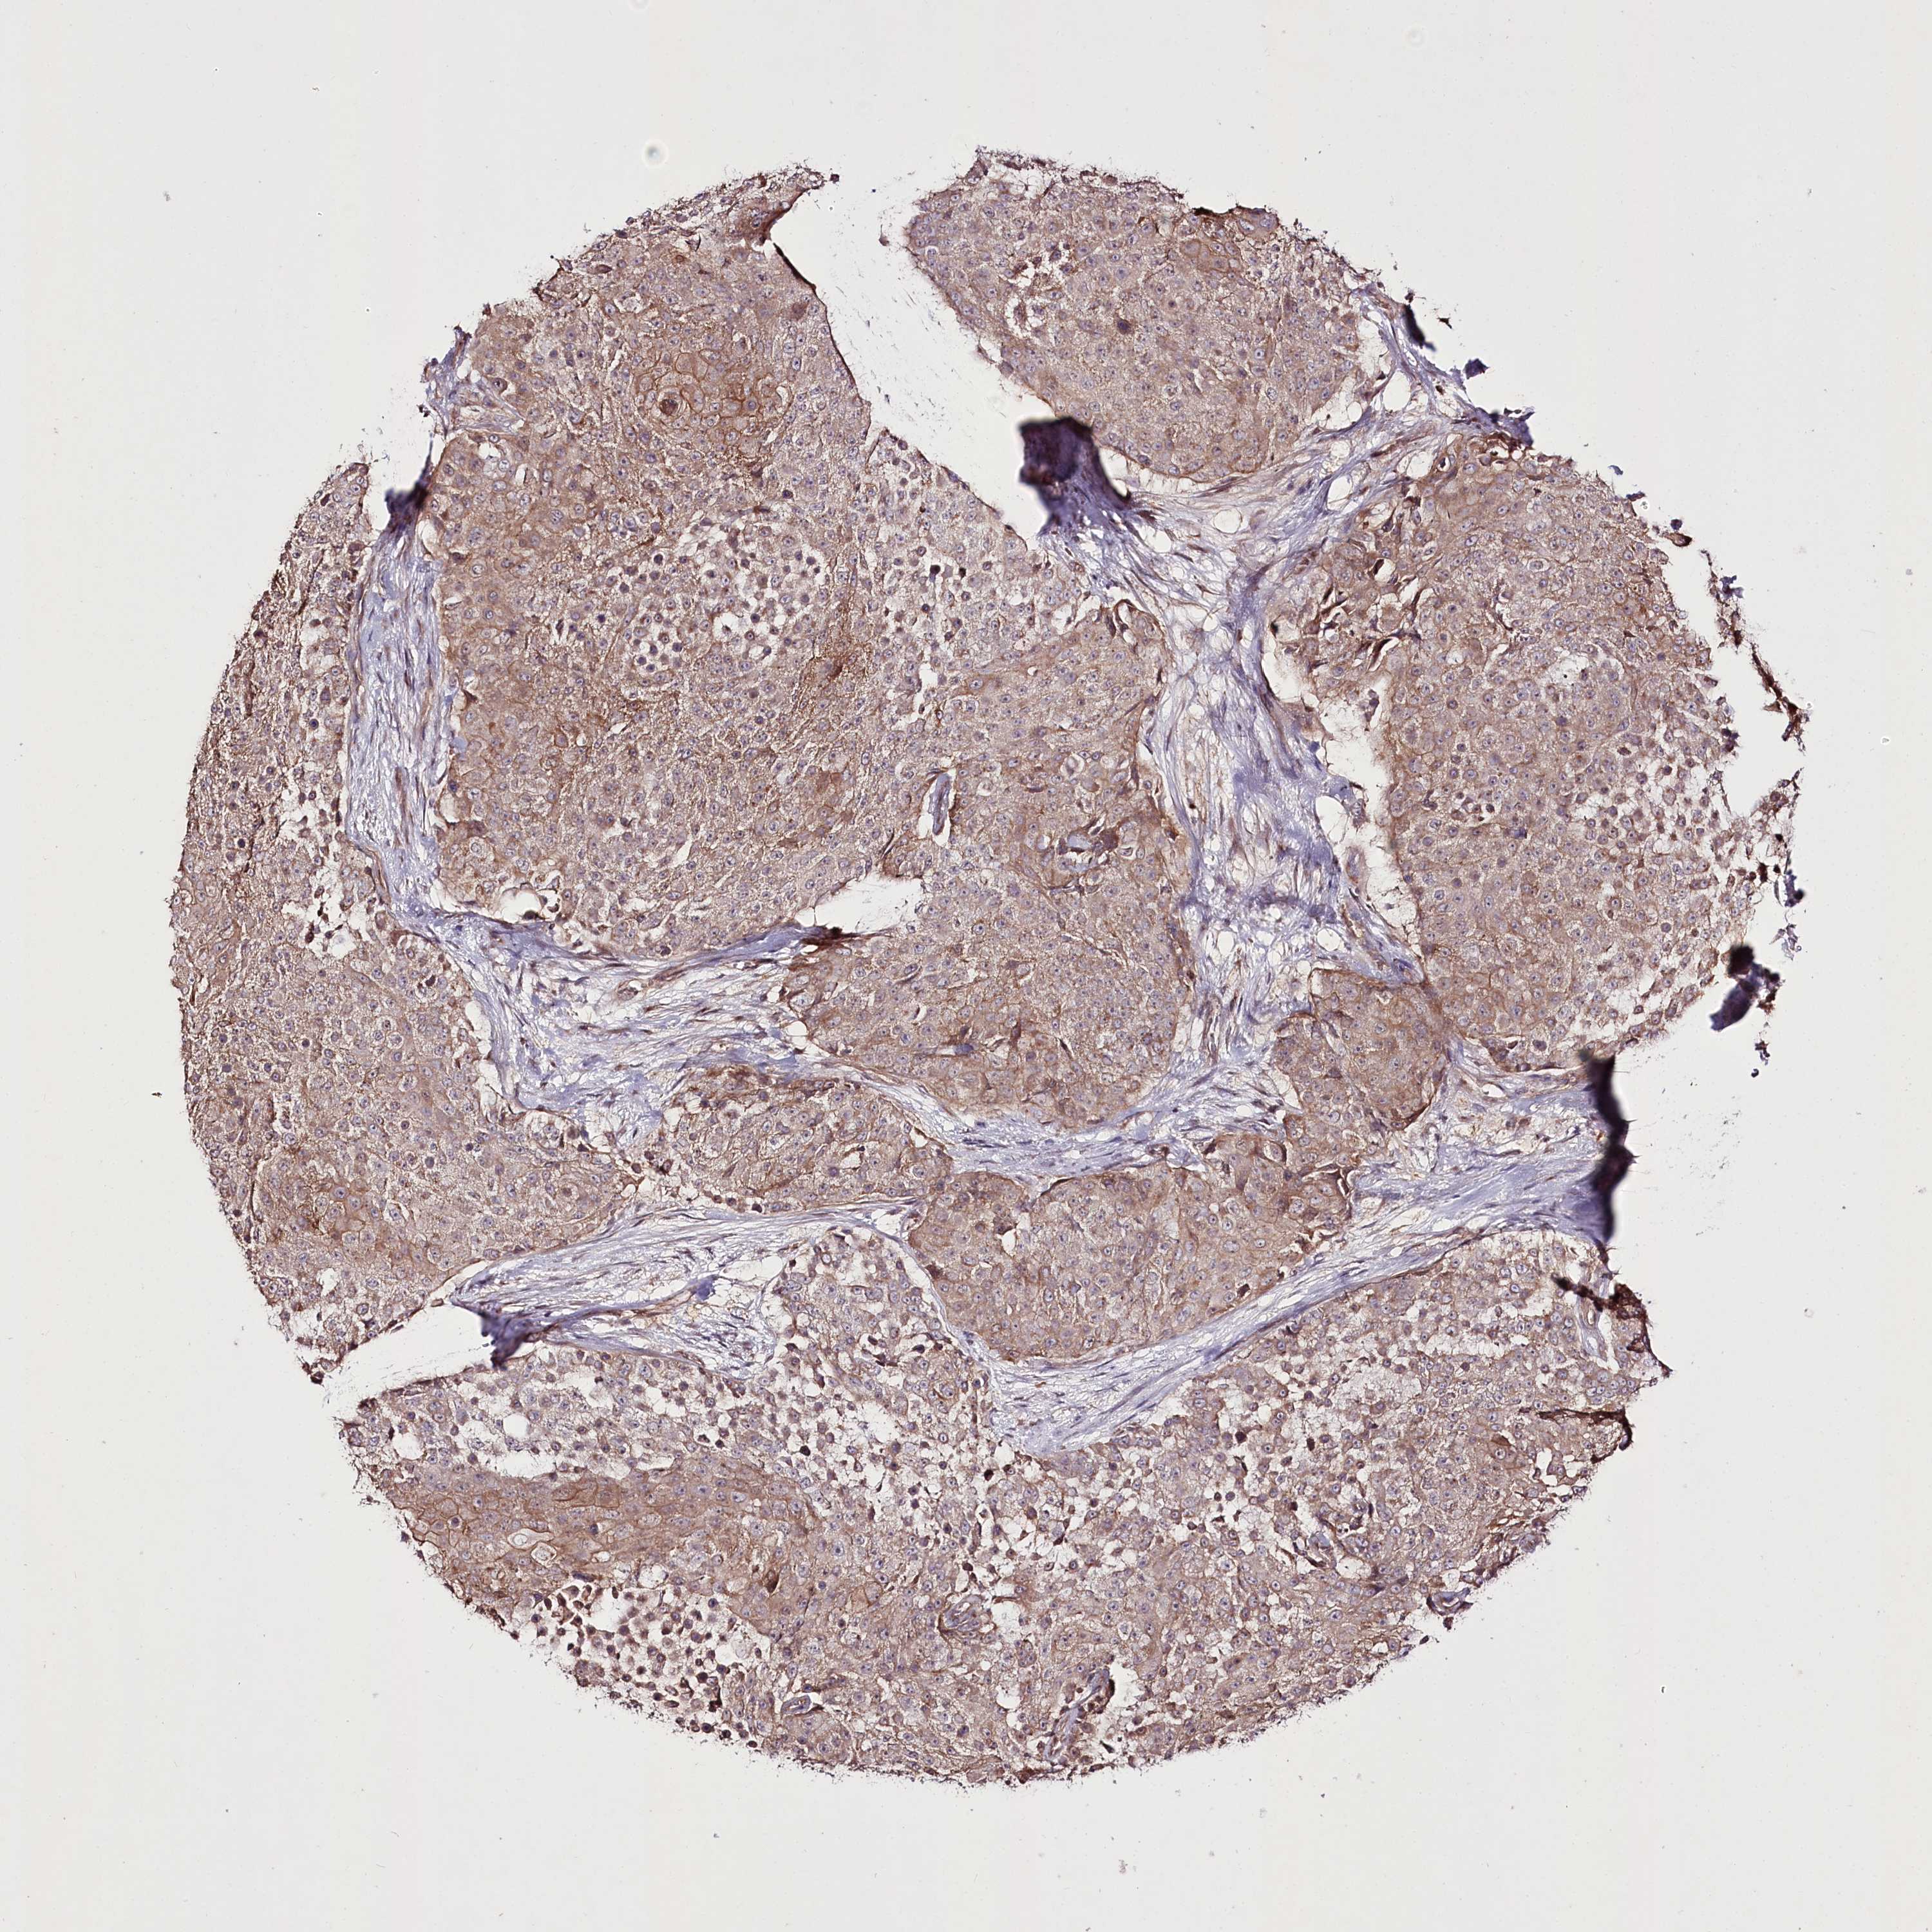

UROTHELIAL CANCER - Protein expressioni

A mouse-over function shows sample information and annotation data. Click on an image to view it in a full screen mode. Samples can be filtered based on level of antibody staining by selecting one or several of the following categories: high, medium, low and not detected. The assay and annotation is described here.

Antibody stainingi

Antibody staining in the annotated cell types in the current human tissue is reported as not detected, low, medium, or high, based on conventional immunohistochemistry profiling in selected tissues. This score is based on the combination of the staining intensity and fraction of stained cells.

Each image is clickable and will lead to virtual microscopy that enables deeper exploration of all samples and also displays staining intensity scores, fraction scores and subcellular localization as well as patient and tissue information for each sample.

Antibody HPA038450

Antibody HPA038451

Staining

High

Medium

Low

Not detected

Intensity

Strong

Moderate

Weak

Negative

Quantity

>75%

75%-25%

<25%

None

Location

Nuclear

Cytoplasmic/membranous

Cytoplasmic/membranous,nuclear

Urothelial carcinoma, High grade

Urothelial carcinoma, Low grade

Urothelial carcinoma, NOS